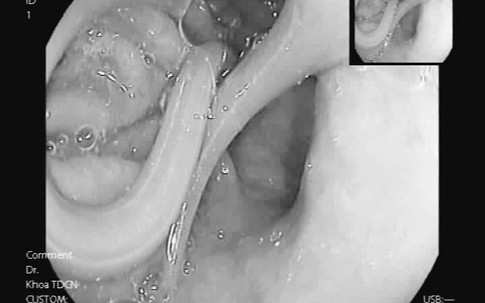

Hiếm gặp: Sán lá gan lạc chỗ, bò ngược lên ngực nữ bệnh nhân trẻ tuổi

Y tếGiadinhNet - Thấy tổn thương ở ngực phải gây đau nhói, chị H (29 tuổi) nghĩ mình bị viêm tuyến vú, áp xe nên nhờ người nặn ra. Bất ngờ, thấy một con sán làm tổ, ngoe nguẩy ký sinh tại đó.